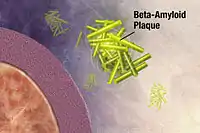

Amyloid hypothesis

In 1991, the amyloid hypothesis postulated that extracellular amyloid beta (Aβ) deposits are the fundamental cause of the disease.[54][55] Support for this postulate comes from the location of the gene for the amyloid precursor protein (APP) on chromosome 21, together with the fact that people with trisomy 21 (Down Syndrome) who have an extra gene copy almost universally exhibit at least the earliest symptoms of AD by 40 years of age.[56][57] Also, a specific isoform of apolipoprotein, APOE4, is a major genetic risk factor for AD. While apolipoproteins enhance the breakdown of beta amyloid, some isoforms are not effective at this task (such as APOE4), leading to excess amyloid buildup in the brain.[58] Further evidence comes from the finding that transgenic mice that express a mutant form of the human APP gene develop fibrillar amyloid plaques and Alzheimer's-like brain pathology with spatial learning deficits.[59]

An experimental vaccine was found to clear the amyloid plaques in early human trials, but it did not have any significant effect on dementia.[60] Researchers have been led to suspect non-plaque Aβ oligomers (aggregates of many monomers) as the primary pathogenic form of Aβ. These toxic oligomers, also referred to as amyloid-derived diffusible ligands (ADDLs), bind to a surface receptor on neurons and change the structure of the synapse, thereby disrupting neuronal communication.[61] One receptor for Aβ oligomers may be the prion protein, the same protein that has been linked to mad cow disease and the related human condition, Creutzfeldt–Jakob disease, thus potentially linking the underlying mechanism of these neurodegenerative disorders with that of Alzheimer's disease.[62]

Both amyloid plaques and neurofibrillary tangles are clearly visible by microscopy in brains of those afflicted by AD.[97] Plaques are dense, mostly insoluble deposits of beta-amyloid peptide and cellular material outside and around neurons. Tangles (neurofibrillary tangles) are aggregates of the microtubule-associated protein tau which has become hyperphosphorylated and accumulate inside the cells themselves. Although many older individuals develop some plaques and tangles as a consequence of ageing, the brains of people with AD have a greater number of them in specific brain regions such as the temporal lobe.[98] Lewy bodies are not rare in the brains of people with AD.[99]

Biochemistry

Alzheimer's disease has been identified as a protein misfolding disease (proteopathy), caused by plaque accumulation of abnormally folded amyloid beta protein and tau protein in the brain.[100] Plaques are made up of small peptides, 39–43 amino acids in length, called amyloid beta (Aβ). Aβ is a fragment from the larger amyloid precursor protein (APP). APP is a transmembrane protein that penetrates through the neuron's membrane. APP is critical to neuron growth, survival, and post-injury repair.[101][102] In Alzheimer's disease, gamma secretase and beta secretase act together in a proteolytic process which causes APP to be divided into smaller fragments.[103] One of these fragments gives rise to fibrils of amyloid beta, which then form clumps that deposit outside neurons in dense formations known as senile plaques.[97][104]